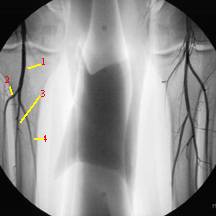

-Nội soi mật tụy ngược dòng ERCP (Endoscopic Retrograde Cholangiography): thành ống mât chủ dãn và đường kính khoảng 1.2cm. phát hiện một vật thể lấp OMC không bình thường. Thực hiện cắt cơ thắt thì phát hiện rất nhiều sán lá chết tại đó và chúng được lấy ra theo thủ thuật bằng một balloon. Sau thủ thuật, các triệu chứng bệnh nhân giảm đi đáng kể, định loại sán lá Fasciola spp.

-Sau 5 ngày, bệnh nhân xuất hiện chảy máu tiêu hóa trên, kiểm tra cấp cứu nội soi cho thấy chảy máu từ OMC. Thực hiện lại ERCP, cho thấy một vùng xa của OMC bị lấp đầy bởi dị vật, không đồng nhất, đường mật dãn nhẹ. Sau khi bóc lấy cục nghẽn, một luồn máu phun raà quyết định chuyển sang mổ bụng cấp cứu;

Nhiễm sán lá gan lớn (SLGL) thường có diễn tiến 2 giai đoạn lâm sàng: giai đoạn cấp chính là lúc mà sán xâm nhập vào nhu mô gan và giai đoạn mạn tính khi chúng xâm nhập vào hệ đường mật. Sau khi tiêu hóa các thức ăn (rau thủy sinh hoặc gan sống có nhiễm ấu trùng), sán sẽ từ tá tràng đến khoang phúc mạc, đục thủng bao gan vào trong hệ đường mật, hoặc đến đường mật thông qua đường máu và hệ bạch huyết. Sau khi đến đường mật, thích hợp cho sán phát triển thành sán trưởng thành. Như vậy, trong giai đoạn cấp bệnh nhân thường biểu hiện sốt, đau hạ sườn (P), gan lớn, tăng bạch cầu eosine và do các dấu chứng này na ná có trong các bệnh khác thì chúng ta thường không chú ý, các triệu chứng nổi mày đay và ngứa tùy thuộc vào sự tiết của sán, giai đoạn tiếp theo có thể là bán cấp, các triệu chứng giảm dần và mất hẳn, chuyển sang giai đoạn mạn tính, biểu hiện các triệu chứng của hệ đường mật, có ứ mật và viêm đường mật do sán định vị trong đường mật, các biến chứng xuất huyết hoặc thủng, loét như thế này là rất hiếm. Trên y văn đã thông báo một số trường hợp, trong đó, 1 ca hình thành vết loét và chảy máu ở OMC tại vị trí đoạn giữa xa của OMC, qua vết loét, sán đi vào nhú bóng Vater, xuyên thủng qua OMC. Trường hợp này là bệnh nhân có cơn đau vùng thượng vị thời gian khá lâu sau thăm dò toàn bộ cho thấy xác sán chết bằng ERCP chỉ ra bệnh đã ở giai đoạn mạn tính, có lẽ đây là trường hợp rất hy hữu bởi vết loét này do sán gây nên (!), cơ chế tạo nên vết loét như thế nào chưa rõ. Trong ca bệnh này thì biểu hiện cũng như những bằng chứng xác thực trên cuộc thăm dò bằng ERCP tương tự như ca bệnh ở Thái Lan (Wong RK và cs., 1985) và 2 ca bệnh ở Thỗ Nhĩ Kỳ (Aksoy DY và cs., 2006).